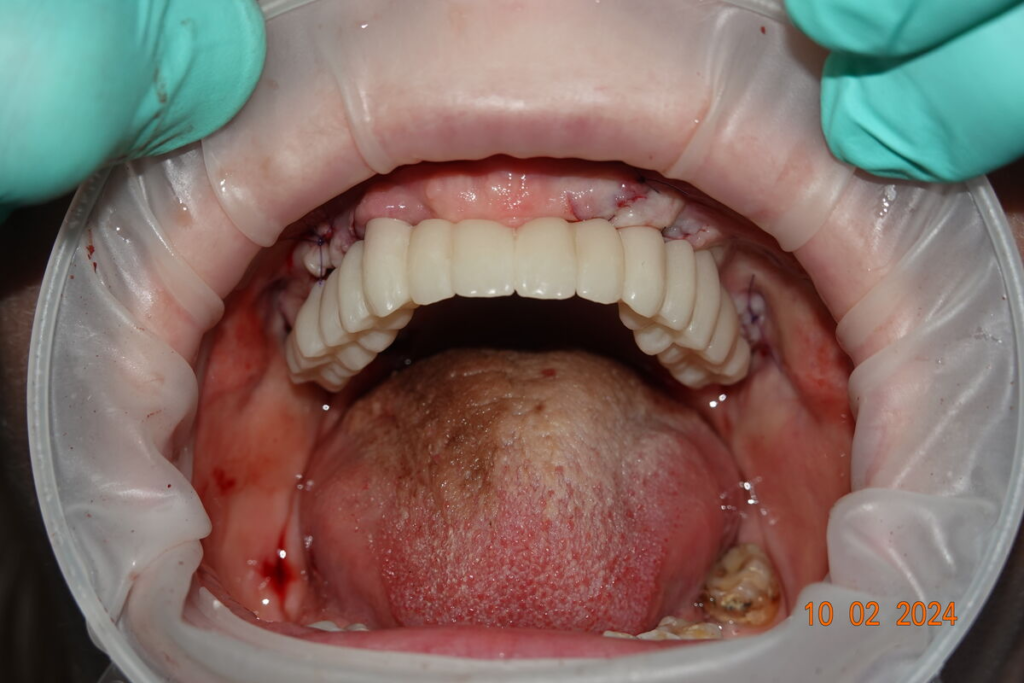

3. Nové zuby tentýž den

Odcházíte s pevnými dočasnými zuby — bez snímatelné protézy.

Můžete mluvit, smát se a jíst měkkou stravu.

Technika All-on-X — I. fáze